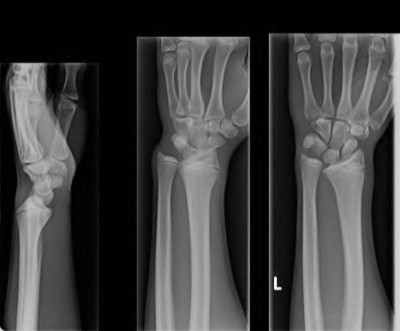

Question 6:

A 22-year-old male falls onto an outstretched hand and sustains a displaced fracture through the proximal pole of the scaphoid. Avascular necrosis of the proximal pole is highly likely due to the disruption of its primary vascular supply. Which vessel provides this critical retrograde perfusion?

Correct Answer: Dorsal carpal branch of the radial artery

Explanation:

The primary blood supply to the scaphoid is from the dorsal carpal branch of the radial artery, which enters the dorsal ridge of the scaphoid at the waist and courses proximally. This retrograde blood flow makes proximal pole fractures highly susceptible to avascular necrosis and nonunion. The superficial palmar branch provides a minor supply (about 20%) to the distal pole.